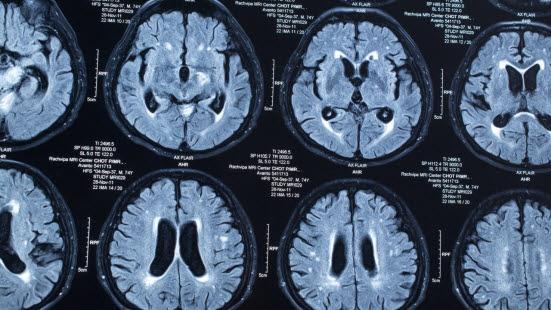

- Hjerneslag er plutselig innsettende tap av funksjoner, såkalte nevrologiske utfall, forårsaket av forstyrrelser i hjernens blodsirkulasjon

- I de aller fleste tilfeller vil årsaken til lammelser være et hjerneslag med sviktende blodtilførsel til deler av hjernen på grunn av en blodpropp (85 prosent) (danner et hjerneinfarkt), mens årsaken sjeldnere (15 prosent) er en blødning fra blodkar i hjernen